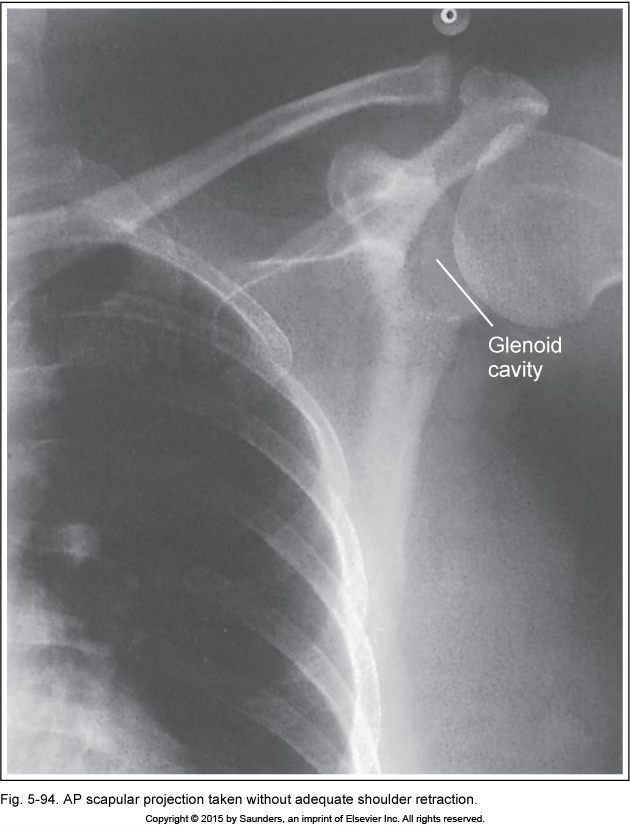

AP scapula

unadequate shoulder retraction